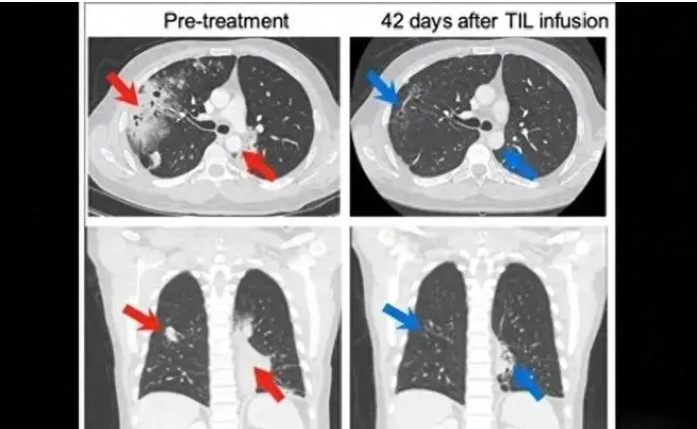

上图为一位在MSK接受治疗的肺癌患者的CT扫描,从两个不同的角度拍摄。这些图像分别展示了患者接受TIL治疗前和治疗6周后的胸部情况。左侧的治疗前图像显示胸腔内有大面积的癌症区域(红色箭头所示)。右侧的治疗后图像显示癌症区域显著缩小(蓝色箭头所示)。CT扫描显示,TIL输注后12周,根据RECIST v1.1标准,部分缓解率为81%。 目前无癌家园免疫细胞临床试验正在招募中,主要治疗黑色素瘤、肺癌、头颈部鳞癌、食管鳞癌、宫颈癌、子宫内膜癌;乳腺癌,卵巢癌,输卵管癌,肾癌,尿路上皮癌等实体瘤。 免疫治疗新纪元,TILs疗法横空出世 肿瘤浸润淋巴细胞(TIL)治疗是一种过继细胞疗法(ACT),涉及从手术切除的癌症组织中分离出自体T细胞,在体外扩增和活化后重新输注到患者体内。 简单来说,TIL疗法相当于从肿瘤这个“战场”上直接招募已经识别并攻击癌细胞的“精英士兵”(淋巴细胞),在体外为他们提供“军事扩张”(大量扩增),然后再将他们送回体内进行更大规模的“战斗”。 这些淋巴细胞——主要是T细胞和B细胞,是免疫系统的重要组成部分。它们在体内不断巡逻,识别不应该存在的细胞包括癌细胞。当癌症发展时,淋巴细胞会识别这些异常细胞并进入肿瘤内部,这些进入肿瘤的淋巴细胞就被称为肿瘤浸润淋巴细胞。 2011年,免疫治疗先驱Rosenberg团队在《Clinical Cancer Research》上发表了一项里程碑式研究:TILs治疗黑色素瘤患者的客观缓解率(ORR)达到56%,完全缓解率高达24%。这为TILs疗法的发展奠定了基础。 2024年2月16日,全球首款TIL疗法Lifileucel获得FDA加速批准,用于治疗PD-1抗体或BRAF抑制剂治疗失败的不可切除/晚期黑色素瘤。这吹响了细胞疗法攻克实体瘤的号角,也为肺癌等其他实体瘤的治疗带来新希望。 除了上述研究提到的非小细胞肺癌外,TILs疗法在黑色素瘤、宫颈癌、胆管癌、结直肠癌、乳腺癌、头颈部、肉瘤、胆囊癌等恶性肿瘤中也显示出巨大潜力。已经发展的各项研究表明,TIL治疗将有待不断改进和发展,最终将成为人类抗癌的新武器。